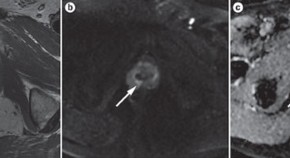

A combined DW-MRI and T2W-MRI approach has been associated with improved accuracy for prostate tumor detection and has been suggested as a tool to guide tissue biopsy. DW-MRI can be used to gather tumor-related information in a noninvasive manner and has potential further roles in active surveillance, evaluating treatment efficacy, and predicting disease recurrence. Validation in large prospective multicenter trials is critical if this technique is to be integrated into current management algorithms for prostate cancer.